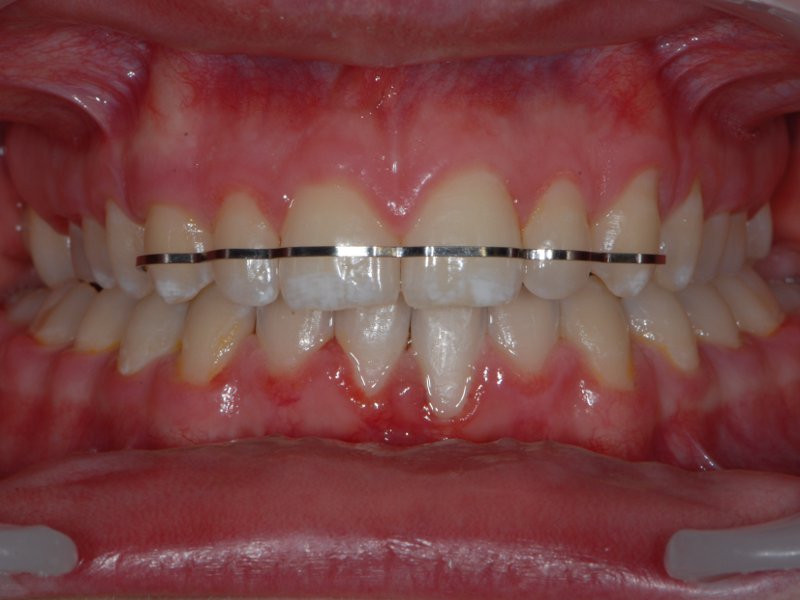

Flatwire retainer